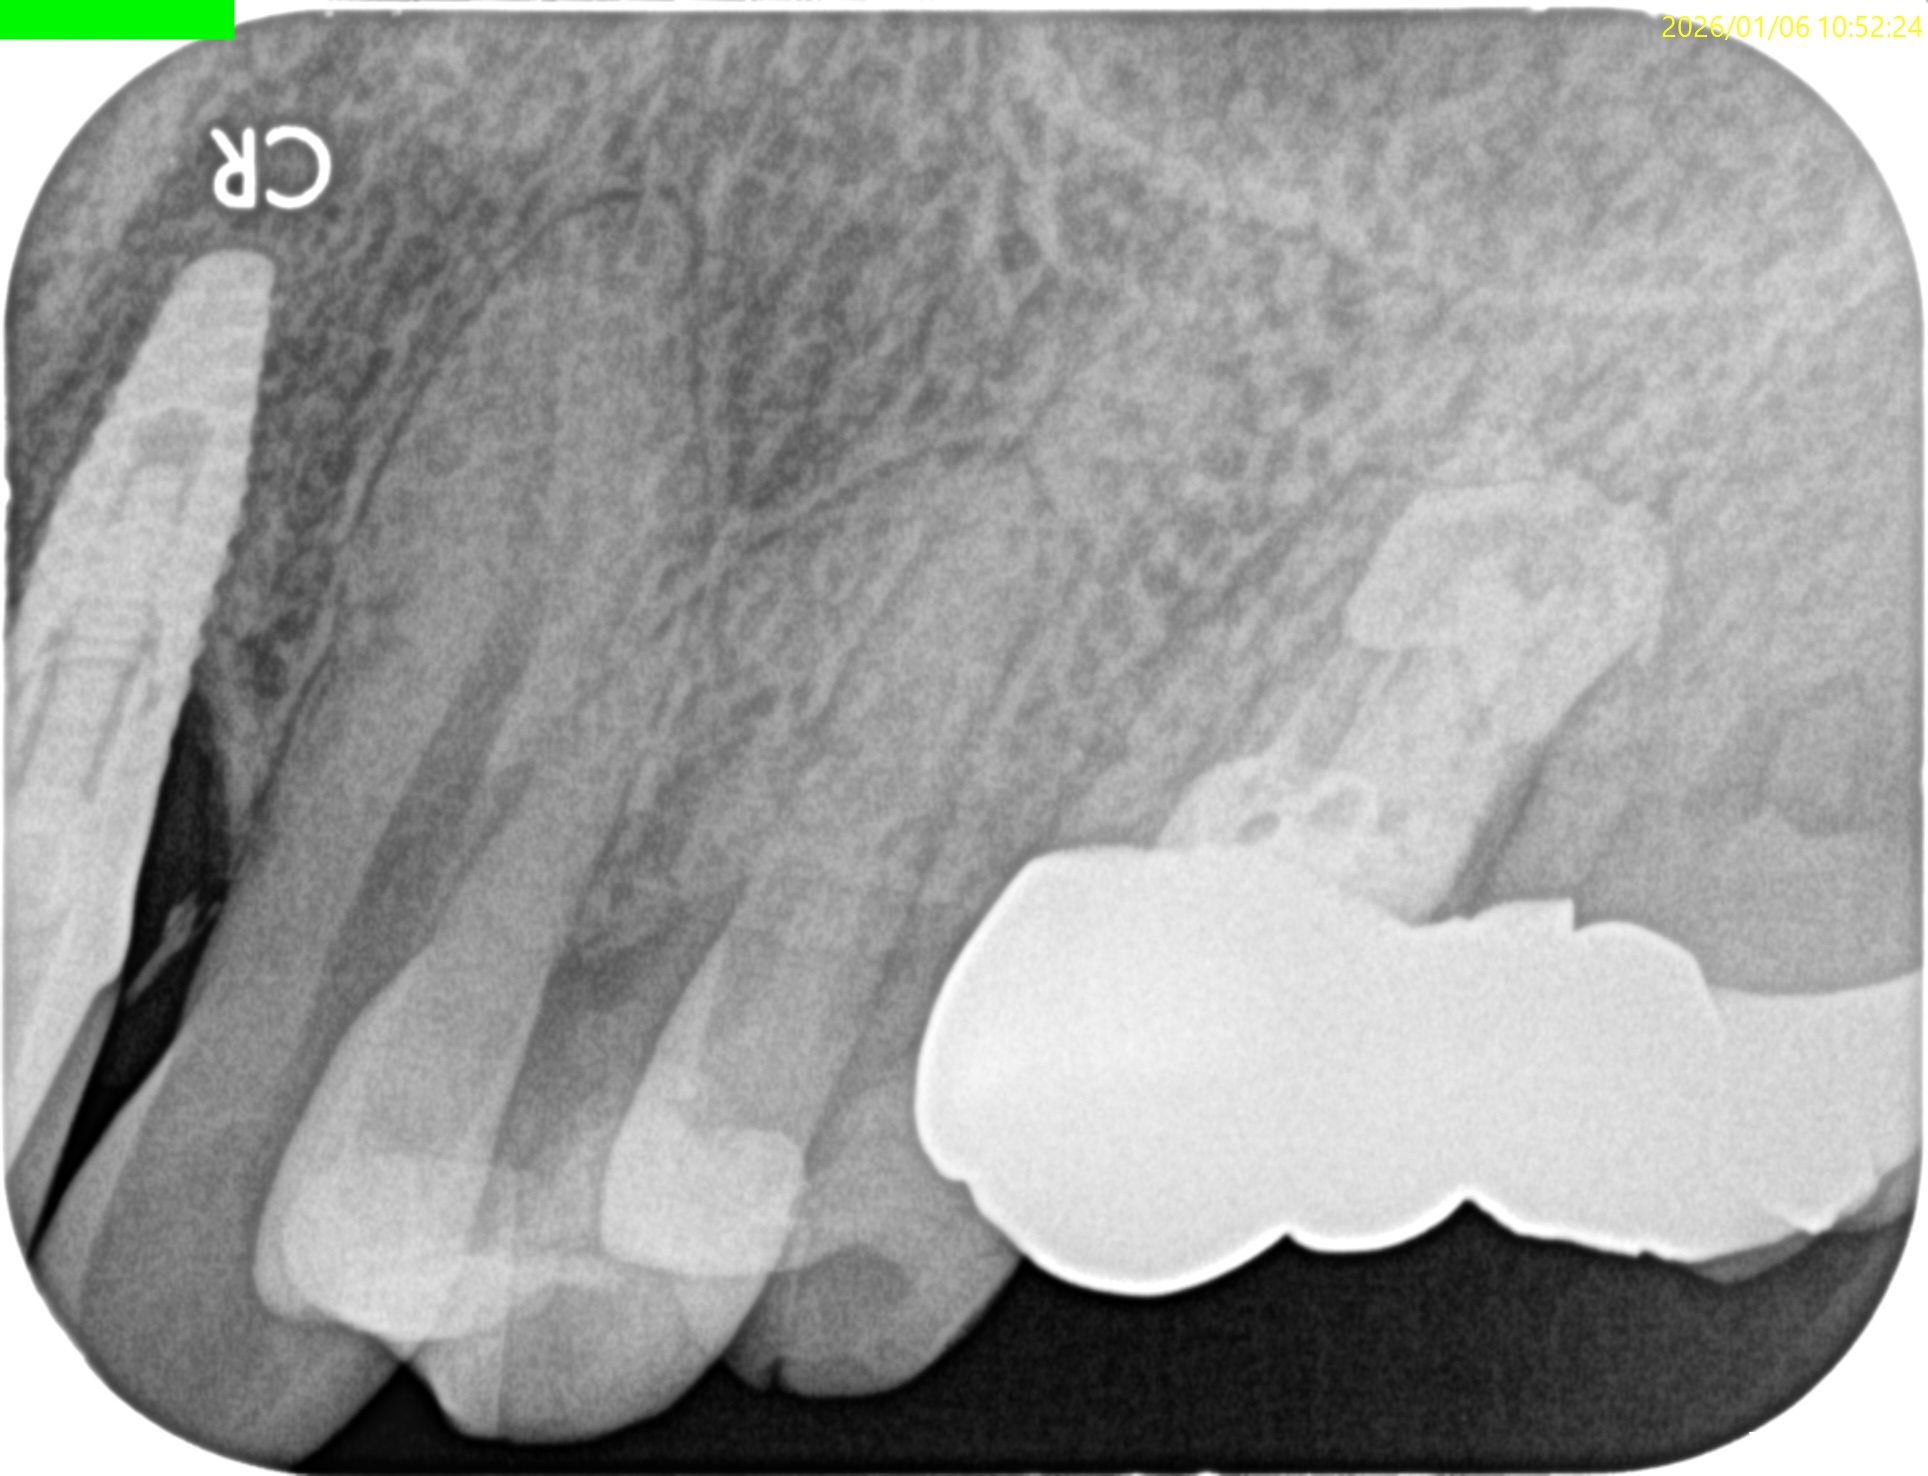

PA, CBCTも撮影した。

#14と同じような症状がある#2,5であるが、

#2

MB

DB

P

#5

B

無傷の#5にも同じような症状がある。

ということは…

#14の咬合痛?のようなものは病気でなく、そう感じるという臨床的状態で, それだからといって治療を要するものではないだろう

ということがわかる。